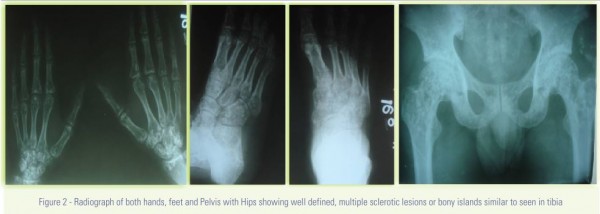

A 34 years male, electrician in came with history of accidental fall from height while working in office leading to development of pain and swelling over left lower leg and ankle .Patient was completely asymptomatic prior to the episode. Patient’s general examination was normal and no abnormality was detected. On examination, patient had swelling and tenderness over lower one-third left leg with bony crepitus and painful ankle movements of left ankle with no distal neuro-vascular deficit. Routine full length left tibia-fibula with ankle radiographs were done (Fig. 1) which showed Ruedi-Allgower classification Type I Pilon fracture (without fibula fracture). Incidental finding seen on the radiograph was well defined, multiple sclerotic lesions or bony islands in lower end of tibia and tarsal bones Radiographs of other parts of body were done which showed presence of similar multifocal bone islands in hand phalanges, metacarpals, carpal bones, metatarsals, tarsals, lower ends of radius, lower ends of ulna and head of femur on both sides (Fig. 2). However ribs , Skull and vertebra were spared (Fig. 3). Lesions were well defined, symmetrical, epiphyseal-metaphyseal involvement of small as well as long bones of body. Patient’s serum calcium, phosphates and alkaline phosphatase levels were normal. Bone scan was normal. Patient had no evidence of any systemic involvement other than skeletal system.

Radiographs show presence of multiple, small, well-defined, variably shaped and widely symmetrically distributed sclerotic areas all over the skeleton with propensity for epiphyseal and metaphyseal involvement and predilection for phalanges(100%), carpal bones(97.4%), metacarpals (92.5%), foot phalanges(87.2%), tarsal bones(84.6%), metatarsals(84.2%), pelvis(74.4%), femur(74.4%), radius(66.7%), ulna(66.7%), sacrum(58.9%), humerus(28.2%), tibia(20.5%) and fibula(2.8%) according to literature with characteristic sparing of skull, ribs and vertebrae [1]. Patients have normal hematological investigations. Patients have a normal bone scan with normal serum calcium, phosphates and alkaline phosphatase levels [8]. Histologically, bone islands consisting of mature bone with thickened trabeculae seen within spongy bone. At the periphery of the lesion, the lesional trabeculae merge with the normal bone and there is no sclerotic rim. Occasionally, woven bone is a minor part of the lesion The condensations of cancellous bone consist of a peripheral area of trabeculae in which osteocytes are scant, and there are no osteoblasts or osteoclasts, together with a central core of irregular trabeculae in which both osteoblasts and osteoclasts are present. The lesions appear to be metabolically active; in the immature skeleton they become denser with growth, but later they may change their sue or even disappear altogether. The precise origin of these abnormal areas remain debatable, but they appear to represent foci of deranged differentiation in cancellous bone [1].